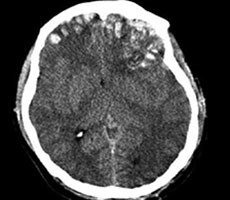

CT scans are essential tools that help medical practitioners detect various medical conditions. Healthcare providers rely on the accuracy of these technologies, because a misdiagnosis could prove fatal. Unfortunately, this vital technology is vulnerable to hackers. Researchers recently designed malware that can add or take away fake cancerous

Source: Hot Hardware – Terrifying Malware Alters CT Scans To Look Like Brain Cancer, Fools Radiologists